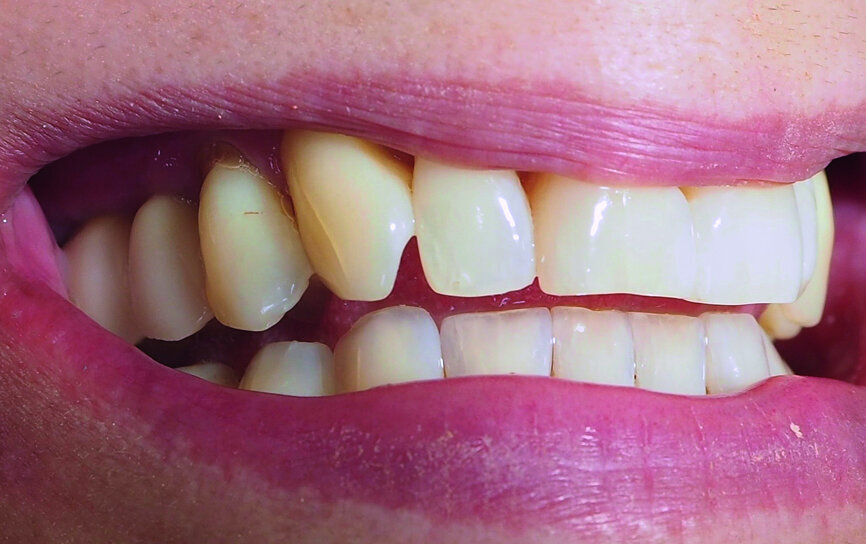

A 52-year-old female patient was concerned about the appearance of her smile. Her upper right first molar and second premolar had been missing for several years (Figs. 1 and 2). She was otherwise a fit and healthy non-smoker.

Fig. 2: Pre-op radiograph.